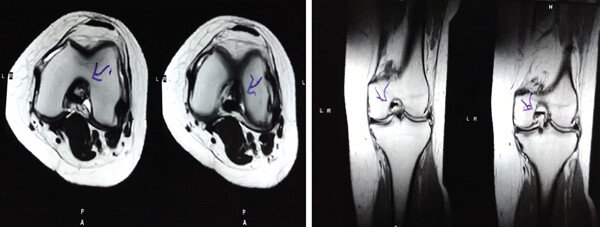

MRI檢查發(fā)現(xiàn)半月板損傷處修復(fù):3D MRI 顯示 2 年時半月板撕裂難以辨別。

結(jié)論:滑膜間充質(zhì)干細(xì)胞移植后,2年的隨訪中,患者的關(guān)節(jié)功能改善,MRI檢查發(fā)現(xiàn)半月板損傷處恢復(fù),沒有發(fā)生導(dǎo)致研究終止的重大不良事件。可以達(dá)到干細(xì)胞治療半月板損傷長期療效的目標(biāo)。